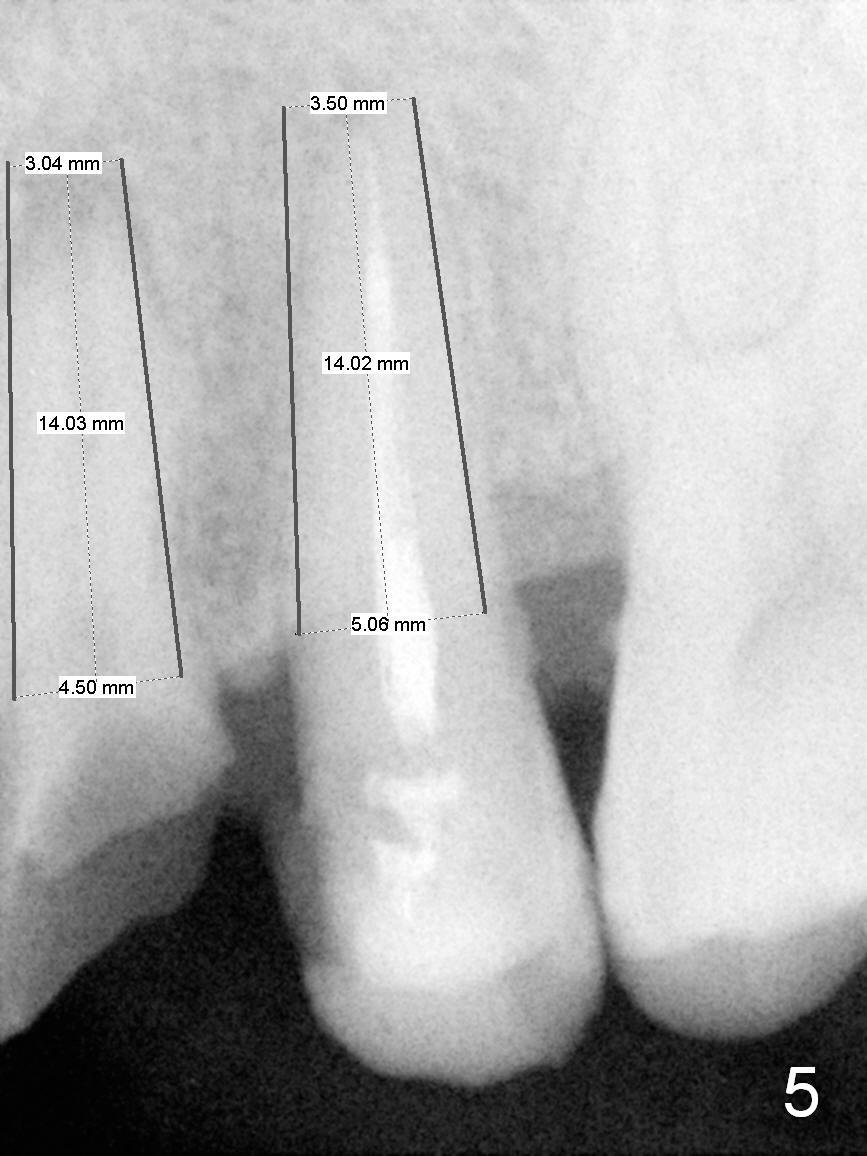

A 45-year-old man presented to our office 8 years ago (Fig.1,2) and got work done somewhere else. He returned yesterday with chief complaint "I might swallow my crowns". Exam shows residual roots at #12,13 (Fig.3,4). The patient has strong jaw bone, suggesting that the bone density is high. Either bone- (Fig.5) or tissue- (Fig.6) level implants will be placed. By time sequence, this case will be assigned to the control group of the antibiotic study. Preop PA does not catch the apices (Fig.3). Take a new one with sensor 1 prior to surgery or panoramus.